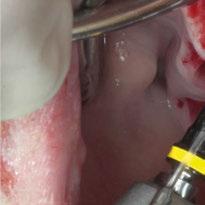

Para ilustrar el proceso, presentamos el caso de una mujer joven diagnosticada de carcinoma adenoide quístico en la región posterior del hemipaladar izquierdo (Figuras 1 y 2). El procedimiento quirúrgico realizado fue una

maxilectomía parcial que incluyó las piezas 24-26 y desde el reborde alveolar hasta la base del cráneo (Figuras 3 y 4). En este caso, la órbita y el globo ocular pudieron ser preservados. La reconstrucción inmediata se realizó mediante un colgajo de músculo temporal homolateral (Figura 5) y el defecto de la fosa temporal fue cubierto mediante una malla de titanio. Posteriormente, la paciente recibió radioterapia (Figuras 6 y 7). 2 años más tarde se diseñó un IS con anclaje en el arbotante nasomaxilar, zona subnasal izquierda

Figura 3. Maxilectomía parcial.

Figura 4. Defecto maxilar tras resección del tumor.

y lo que se pudo preservar del hueso malar. Se añadió una malla sinterizada infraorbitaria para dar volumen a la mejilla y se planificaron dos brazos de conexión que emergieran en las posiciones 24 y 26 de forma subgingival (Figuras 8 y 9). La superficie interna que apoyaba en el hueso era de titanio microrrugoso, y la superficie externa y conectores de titanio pulido y hexágono externo universal (Figuras 10 y 11). La cirugía se hizo bajo anestesia general en infiltración con anestesia local (4% articaína, 1:100.00 epinefrina), levantando el

colgajo cutáneo de la mejilla por vía intraoral, preservando el colgajo temporal para no comunicar con el remanente de la cavidad naso maxilar (Figura 12). Se emplearon 10 tornillos de osteosíntesis de 1,9 mm y la estabilidad primaria obtenida fue excelente (Figura 13)